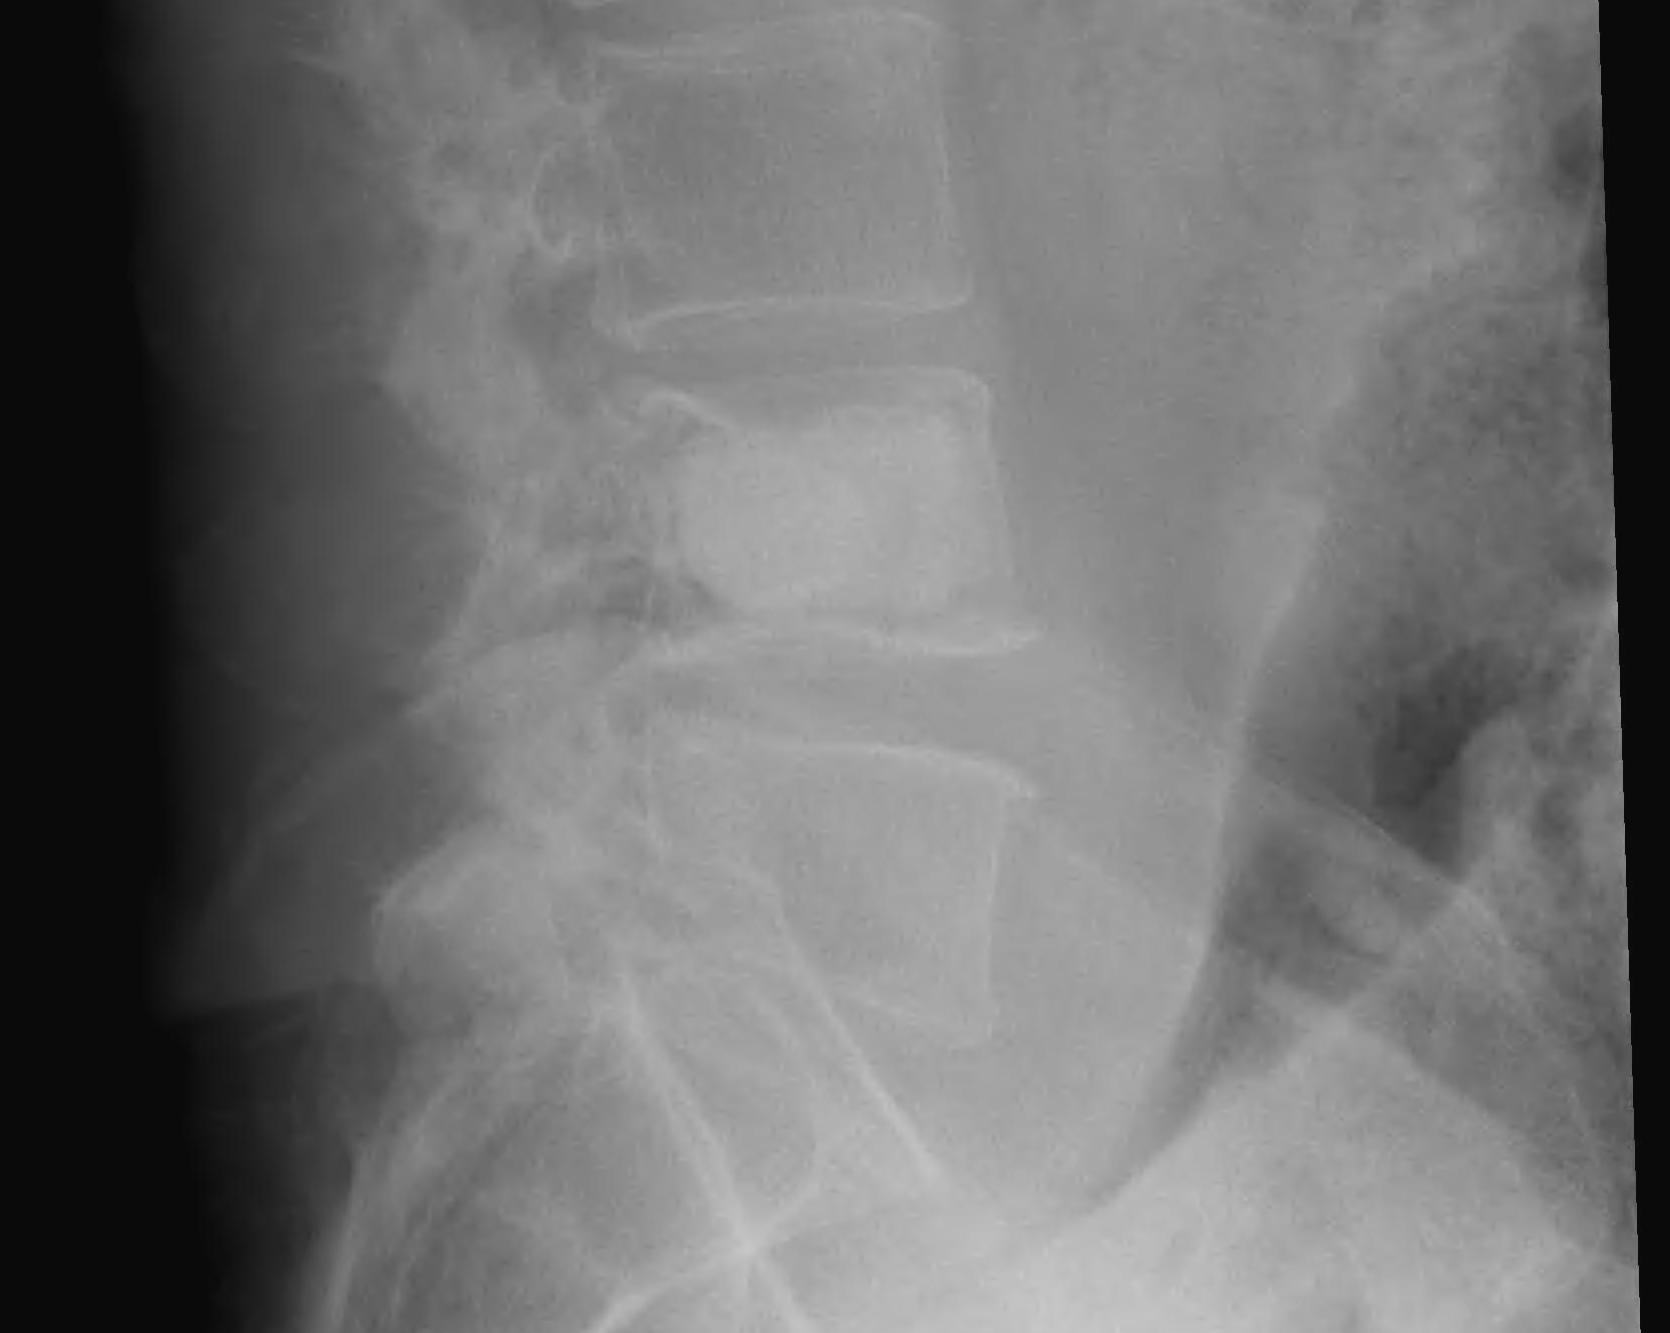

X-ray

75% have abnormality

Winking Owl Sign / Pedicle loss on AP

Lytic / Sclerotic lesion

- need 30% bone loss to see lytic area

Vertebral body collapse